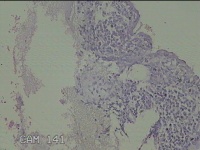

宫颈管内膜

性别

女

年龄

45岁

临床诊断

子宫异常出血 子宫内膜Ca?右卵巢囊肿

一般病史

阴道流血44天。

标本名称

大体所见